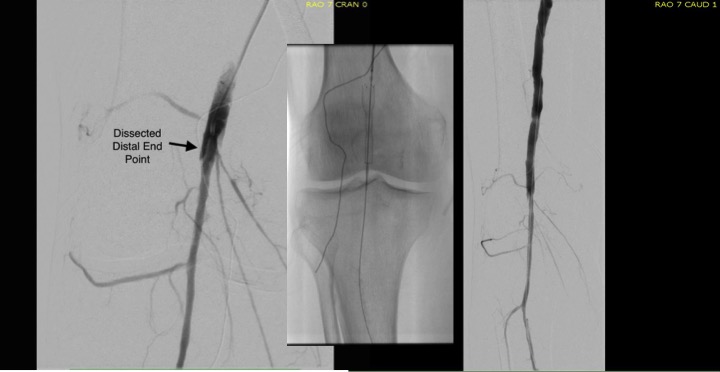

I contacted LeMaitre Vascular and got in touch with your representative, L. Fisher, who promptly sent the Moll Ring Cutters I needed to perform a remote endarterectomy of the patient’s occlusive external iliac and superficial femoral artery plaque. The technical details of remote endarterectomy are have been covered in my blog (https://vascsurg.me/?s=endore), but in the end, through a 7cm incision in the groin (don’t believe the hype, this is minimally invasive), I restored his arteries to their original open condition. Shown below are the results. It was with great sadness that I heard that the LeMaitre Vascular equipment being sent were the last of the stock available in North America. The patient did very well, with the operation completed well before lunch, and is recovering rapidly from his small wound and big rescue. He gets to walk out of the hospital on two legs, but also with the surety that he avoided a major bypass operation, and avoided the short term gains of stenting from the aorta to the profunda -more peel packs and landfill items and a dubious long term durability. Hey, I even used a XenoSure patch on the common femoral.